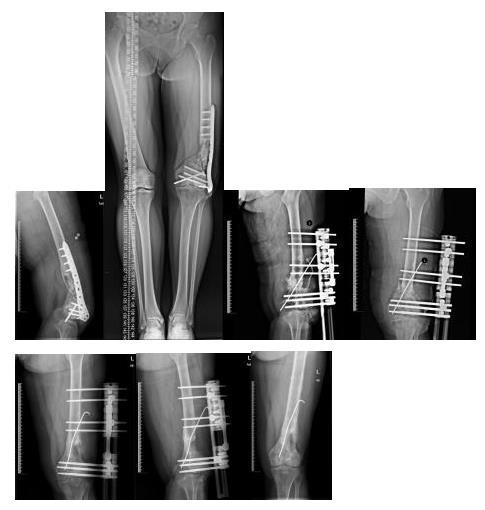

林某 车祸伤致:右侧股骨下段开放性粉碎骨折并10cm骨缺损,左下肢股骨下段粉碎性骨折

右下肢

左下肢